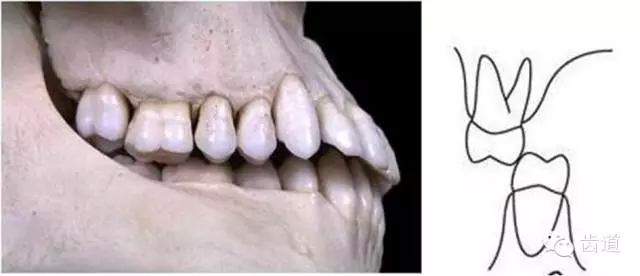

前牙有切道與切道斜度

切道:下前牙切緣前伸的軌道

切道斜度:切道與水平面所成的角度